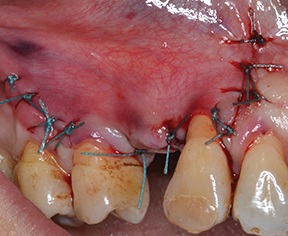

The flap was then closed with a combination of horizontal mattress and interrupted 4-0 polyester sutures (Fig. 20).

Fig. 20: Recipient site closed with double-layer sutures